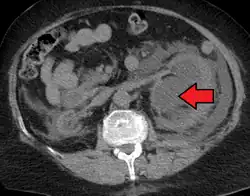

CT scan of bilateral hydronephrosis due to a bladder cancer -

Massive hydronephrosis as marked by the arrow -